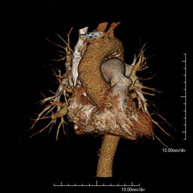

- Angio-TC Aorta torácica Prueba diagnóstica que consiste en el estudio de la aorta torácica (principal arteria del tórax) mediante el empleo de un equipo de TC (Tomografía Computarizada). Esta técnica requiere el empleo de contraste yodado, y proporciona imágenes de alta definición anatómica. El uso del TCMD (TC Multidetector) acorta el tiempo de exploración, disminuye la dosis de radiación y mejora la calidad de la imagen. Gracias a los múltiples detectores, en determinados estudios se puede acoplar la obtención de la imagen con el latido cardíaco, técnica que permite el estudio de la válvula aórtica y de la raíz de la arteria aorta (primeros centímetros), donde el latido del corazón suele provocar múltiples artefactos de movimiento. Prueba diagnóstica que consiste en el estudio de la aorta torácica (principal arteria del tórax) mediante el empleo de un equipo de TC (Tomografía Computarizada). Esta técnica requiere el empleo de contraste yodado, y proporciona imágenes de alta definición anatómica. El uso del TCMD (TC Multidetector) acorta el tiempo de exploración, disminuye la dosis de radiación y mejora la calidad de la imagen. Gracias a los múltiples detectores, en determinados estudios se puede acoplar la obtención de la imagen con el latido cardíaco, técnica que permite el estudio de la válvula aórtica y de la raíz de la arteria aorta (primeros centímetros), donde el latido del corazón suele provocar múltiples artefactos de movimiento.

- Angio TC- aorta toràcica Prova diagnòstica que consisteix en l'estudi de l'aorta toràcica (principal artèria del tòrax) mitjançant l'ús d'un equip de TC (Tomografia Computeritzada). Aquesta tècnica proporciona imatges d'alta definició anatòmica. En la majoria de casos és necessari l'ús de contrast iodat. L'ús del TCMD (TC Multidetector) escurça el temps d'exploració, disminueix la dosi de radiació i millora la qualitat d'imatge. Gràcies als múltiples detectors en determinats estudis es pot afegir l'obtenció de la imatge amb el batec cardíac, tècnica que permet l'estudi de la vàlvula aòrtica i de l'arrel de l'artèria aorta (primers centímetres), on el batec del cor acostuma a provocar falses imatges a causa del moviment. Prova diagnòstica que consisteix en l'estudi de l'aorta toràcica (principal artèria del tòrax) mitjançant l'ús d'un equip de TC (Tomografia Computeritzada). Aquesta tècnica proporciona imatges d'alta definició anatòmica. En la majoria de casos és necessari l'ús de contrast iodat. L'ús del TCMD (TC Multidetector) escurça el temps d'exploració, disminueix la dosi de radiació i millora la qualitat d'imatge. Gràcies als múltiples detectors en determinats estudis es pot afegir l'obtenció de la imatge amb el batec cardíac, tècnica que permet l'estudi de la vàlvula aòrtica i de l'arrel de l'artèria aorta (primers centímetres), on el batec del cor acostuma a provocar falses imatges a causa del moviment.